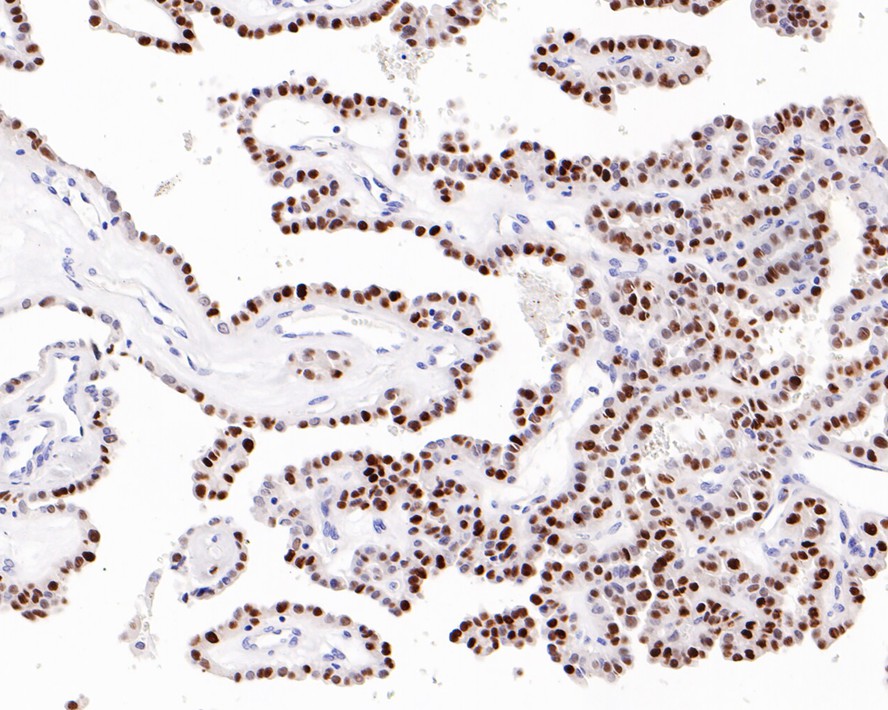

Catalog# HA601017

p21 Mouse Monoclonal Antibody [A8C12]

IHC-P

Human